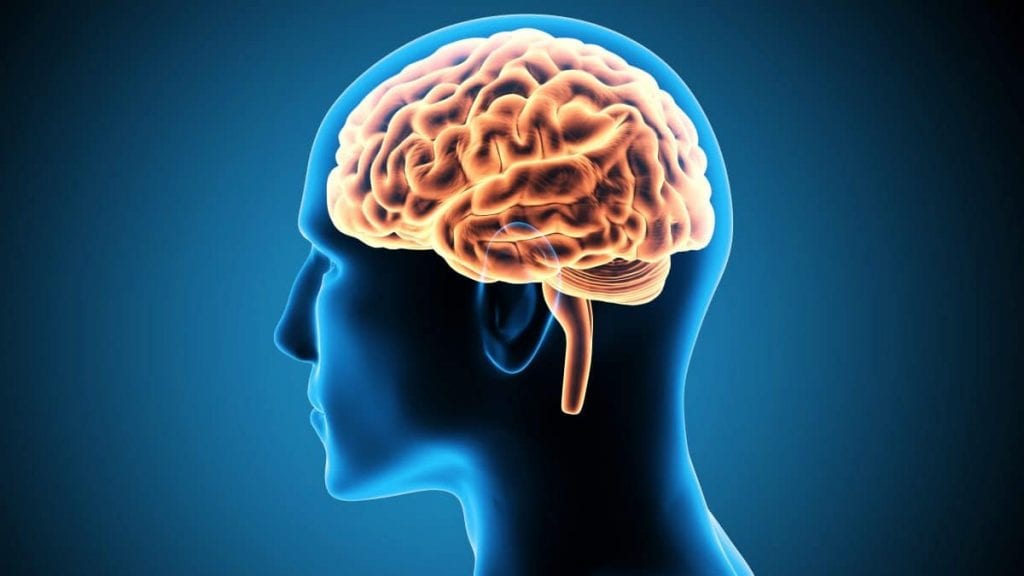

Órgãos do Sistema Nervoso

O sistema nervoso é responsável por garantir a percepção de estímulos internos e externos e gerar respostas a esses estímulos. Em suma, é graças a esse sistema, que somos capazes de memorizar, ter coordenação, falar, sentir, ver e aprender.

Portanto, vamos conhecer os órgãos que formam o sistema nervoso:

Cérebro

O cérebro é o órgão mais importante do sistema nervoso, sendo responsável pela produção de hormônios, bem como o transporte, organização e armazenamento de informações.

Cerebelo

O cerebelo é um órgão localizado abaixo do cérebro. Ele possui funções muito importantes como o movimento, o reflexo, a contração dos músculos e o equilíbrio do organismo.

Medula Espinhal

A medula espinhal é cordão cilíndrico localizado na coluna vertebral, no canal interno das vértebras. Ela tem como principal função a produção e condução de impulsos nervosos do organismo para o cérebro. Ou seja, é a medula espinhal que faz a comunicação entre o corpo e o sistema nervoso.